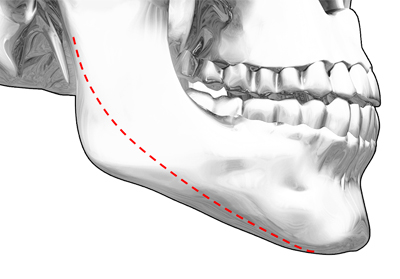

CASE 01 긴곡선절골술

CASE 01 긴곡선절골술얼굴 아랫부분이 넓고

각져보이는 경우 -

수술 전

수술 전 -

입안 최소절개로 절제 공간 확보 후,

신경선을 피해 턱뼈 절제 -